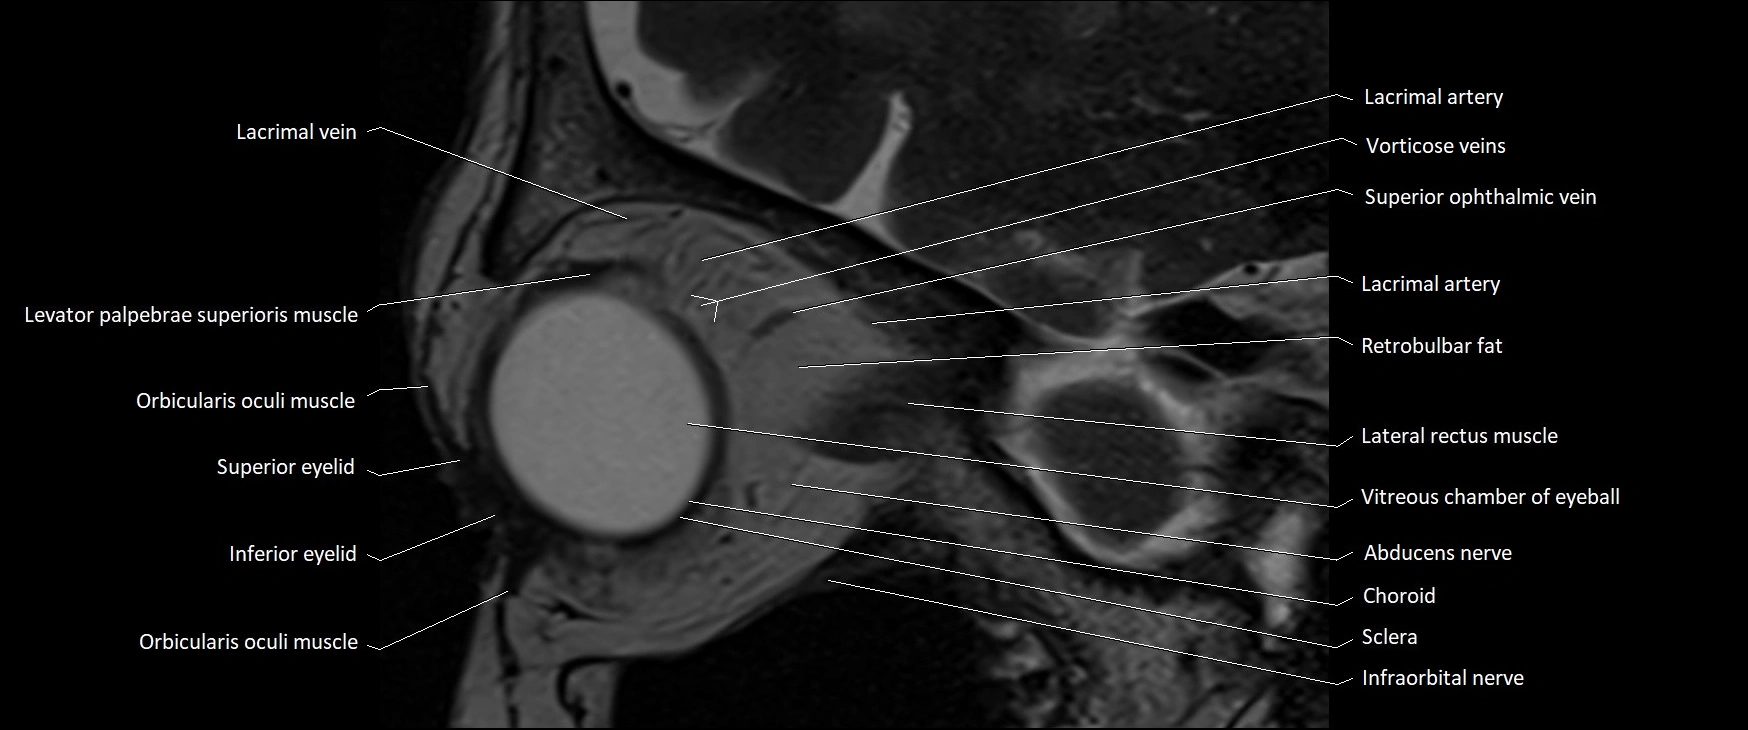

MRI images